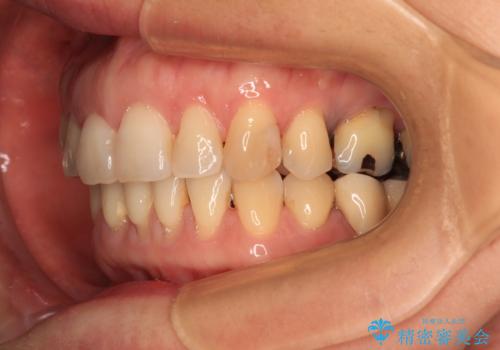

- 飛び出した上顎前歯と正中のズレを気にして来院された患者様です。

上顎正中が右側にずれていたので、むし歯が酷く抜歯が必要な左側臼歯を抜歯して正中を改善することとしました。

左下には新しいセラミックのブリッジが装着されていたため、ブリッジを壊さずに改善できるところまで咬み合わせを改善していくこととしました。

右上小臼歯は銀歯が装着されており、ワイヤー矯正の装置が装着できないため、事前に仮歯に変えてから矯正治療を行い、その後オールセラミッククラウンにて補綴治療を行いました。